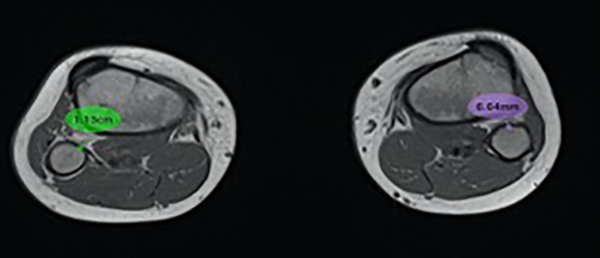

El paciente refería nunca haber requerido una maniobra de reducción para la inestabilidad tibioperonea proximal, simplemente con el cese de la actividad aliviaba el dolor y “desaparecía” el resalto óseo que percibía. Se realizó radiografía de rodilla frente y perfil en la que se pudo apreciar la pérdida parcial de las relaciones articulares entre la tibia y el peroné proximal (fig. 1). Se completó el estudio imagenológico con una resonancia magnética (RM) donde se observó rotura intrasustancia del ligamento tibioperoneo proximal (LTPP) (fig. 2).

Figura 1: Radiografía oblicua interna y externa de rodilla derecha. Se puede observar cómo el peroné se encuentra lateralizado y posterior con respecto a la tibia, sugestivo de lesión de la articulación tibioperonea proximal.

Figura 2: Resonancia magnética de ambas rodillas. Corte axial en el que se evidencia y cuantifica con más precisión la lesión del ligamento tibioperoneo proximal derecho, se observa un aumento de la distancia, edema y su discontinuidad.